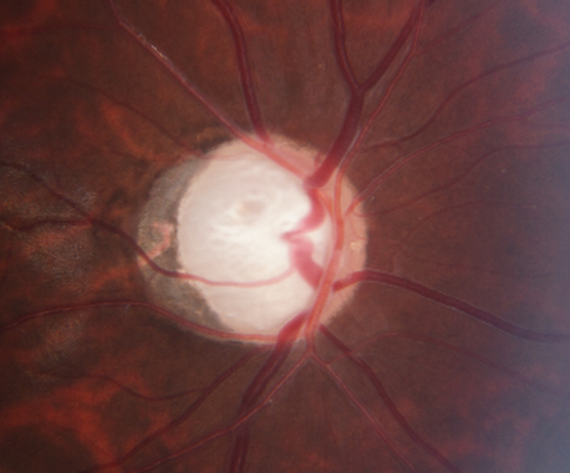

篩查是早期發(fā)現(xiàn)青光眼的重要手段。“視神經(jīng)一張照,青光眼早知道”,眼底照相是青光眼篩查的重要檢查項目。溫醫(yī)大附屬眼視光醫(yī)院梁遠波團隊自2014年起開展的青光眼社區(qū)篩查證實,在中國實施以人群為基礎的青光眼篩查具備良好的成本效益比,值得推廣。

圖 | 青光眼患者眼底照相(晚期青光眼)

青光眼雖然無法從根本上治愈,但是可防可治的,早發(fā)現(xiàn)、早診斷、早治療是保持視功能的關鍵。您給您的視神經(jīng)拍過照了嗎?